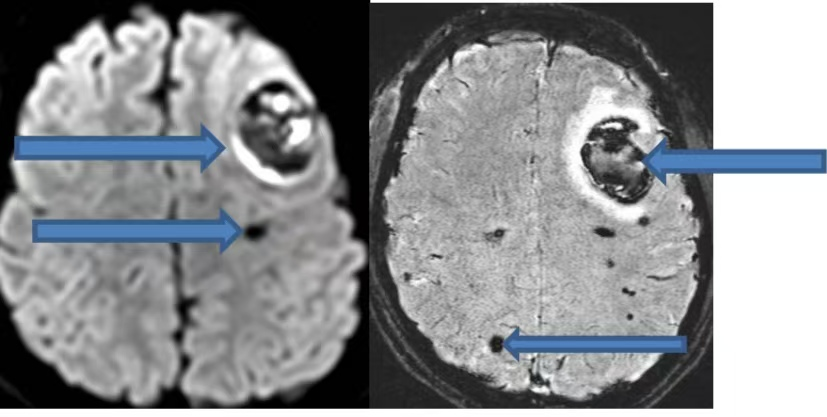

在今年的出院隨訪工作中,我們遇到了這樣一個病例:一位此前被診斷為“顱內海綿狀血管瘤”的年輕人,因癲癇再次發作接受了外科手術,切除了導致癲癇的病灶。這個致癲灶就是導致癲癇發作的“隱形推手”——顱內海綿狀血管瘤。以下通過這個病例,我們逐步揭開“顱內海綿狀血管瘤”的神秘面紗。 這位20歲的小伙在吃飯時突發肢體抽搐、意識喪失、跌倒,意識轉清后完善頭CT發現“左側額葉出血”。當時我們懷疑是瘤卒中,也就是說,小伙顱內長有一個腫瘤,且出血局限于腫瘤內部(如下圖CT所示)。 為了進一步明確腫瘤性質,隨后進行的磁共振檢查顯示:腦內存在多發異常信號影,影像科考慮為多發海綿狀血管瘤。這并非傳統意義上的實質性腫瘤,海綿狀血管瘤是一種血管畸形。在這些血管瘤中,最大的一個位于額葉,且內部發生了出血(如下圖所示)。 最后又完善了磁共振增強檢查,考慮左側額葉血管畸形伴出血(如下圖)。 經省內專家會診,最終診斷:顱內海綿狀血管瘤,并建議使用抗癲癇藥物。 下面,我們來簡單了解一下海綿狀血管瘤: 一 什么是海綿狀血管瘤(CMs) 中樞神經系統海綿狀血管瘤(CMs)是一種先天性血管畸形,分為家族遺傳病例和散發病例。其在顱內血管畸形中占比10%-25%,僅次于腦動靜脈畸形。CMs具有一定的生長能力,在對家族型腦內CMs病例的定期隨訪中發現,每個病例每年可能新增0.4 - 2.7個腦內CMs病灶。 家族遺傳型病例與基因突變相關,散發病例可能與放射線、外傷、顱內感染等外界誘發因素有關。 二 CMs的臨床表現 最常見的臨床表現為癲癇、腦內出血和無近期出血影像學證據的局灶性神經功能缺損。還有20%-50%的腦內CMs屬于無癥狀性,常因腦磁共振的廣泛應用而被偶然發現。 三 CMs的影像學診斷 CMs在CT上表現為邊界清楚的圓形或類圓形的高密度影。CT對體積較小的腦內CMs不敏感,并非腦內CMs最好的檢查手段,臨床上更適合用于急性血腫、占位效應和腦積水的緊急診斷。但反復CT檢查的電離輻射存在促進增加新發腦內CMs的風險,所以當CT初步懷疑腦內CMs后即應進行MRI檢查,且在隨訪觀察中繼續選擇磁共振。 MRI對腦內CMs的檢出敏感性極高,且無創,被推薦為首選的影像學檢查方法,能夠顯示常規序列無法顯示的微小病灶。 DSA檢查中CMs病灶一般不顯影,故DSA在腦內CMs診斷中的作用非常有限。 四 顱內海綿狀血管瘤的治療 外科手術治療 外科手術被認為是腦內CMs最有效的治療方式,但手術切除的指征,仍存在爭議。對于無癥狀的腦內CMs,尤其位于功能區、深部或腦干的無癥狀病灶,一般主張采取保守治療。 手術是控制癲癇發作最有效的方式,可優先考慮手術切除病灶及周圍含鐵血黃素沉積帶;若單藥治療無法控制癲癇發作,也可考慮手術。 立體定向放射外科治療 立體定向放射外科可作為一種治療選擇,應用于功能區、腦深部及腦干癥狀性腦內CMs;無癥狀的和易于手術的癥狀性腦內CMs,均不建議選擇。 內科處理 顱內海綿狀血管瘤相關性癲癇的藥物控制率可達到50%-60%,因此患者一旦確診,即需開始使用抗癲癇藥,同時要注意避免易誘發癲癇的藥物和活動。 腦內CMs相關頭痛的發生率可能高達52%。對于同時患有腦內CMs且符合偏頭痛診斷標準的患者,建議進行標準的偏頭痛治療,非甾體類抗炎藥是安全有效的選擇。 特殊群體顱內CMs的管理 通常情況下,腦內CMs患者是可以選擇妊娠的,但需要進行遺傳咨詢,對于CMs相關性癲癇患者需要調整抗癲癇藥物以降低致畸風險。 10歲以下兒童更容易因輻射誘發新生腦內CMs,所以應盡可能避免反復CT和X線檢查。